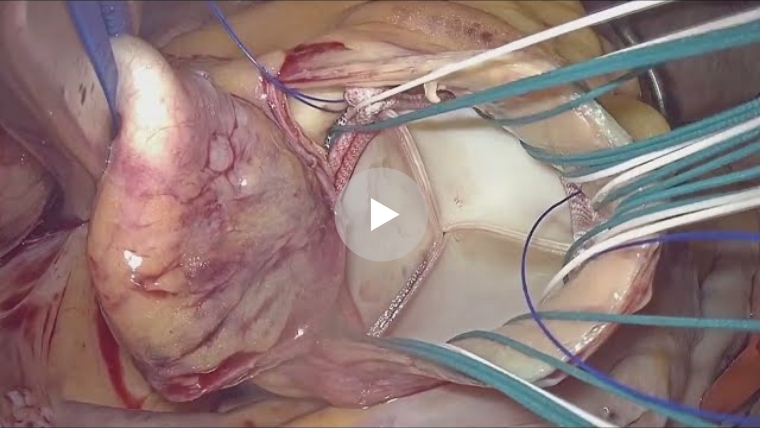

手術では悪くなった弁を切り取り、新しく人工弁を糸で縫い合わせていきます。手術は人工心肺装置を使い、心臓をいったん止めた上で行います。

僧帽弁は2つの弁と、心臓から弁を引っ張っている腱索というひも状の部分から成り立っています。手術では、切れた腱索の代わりに新しい人工腱索で補強したり、壊れた部分を切ったり縫い合わせたりして修復した後、弁の周りに特殊なリングを縫いつけて形を整えます。弁置換のようにワーファリンの内服は必要でなく、心臓の機能を温存でき長期成績も良好なため、弁形成術を第一選択としています。

当院では、僧帽弁形成術を行う場合には可能な限り全例に内視鏡手術で行っております。